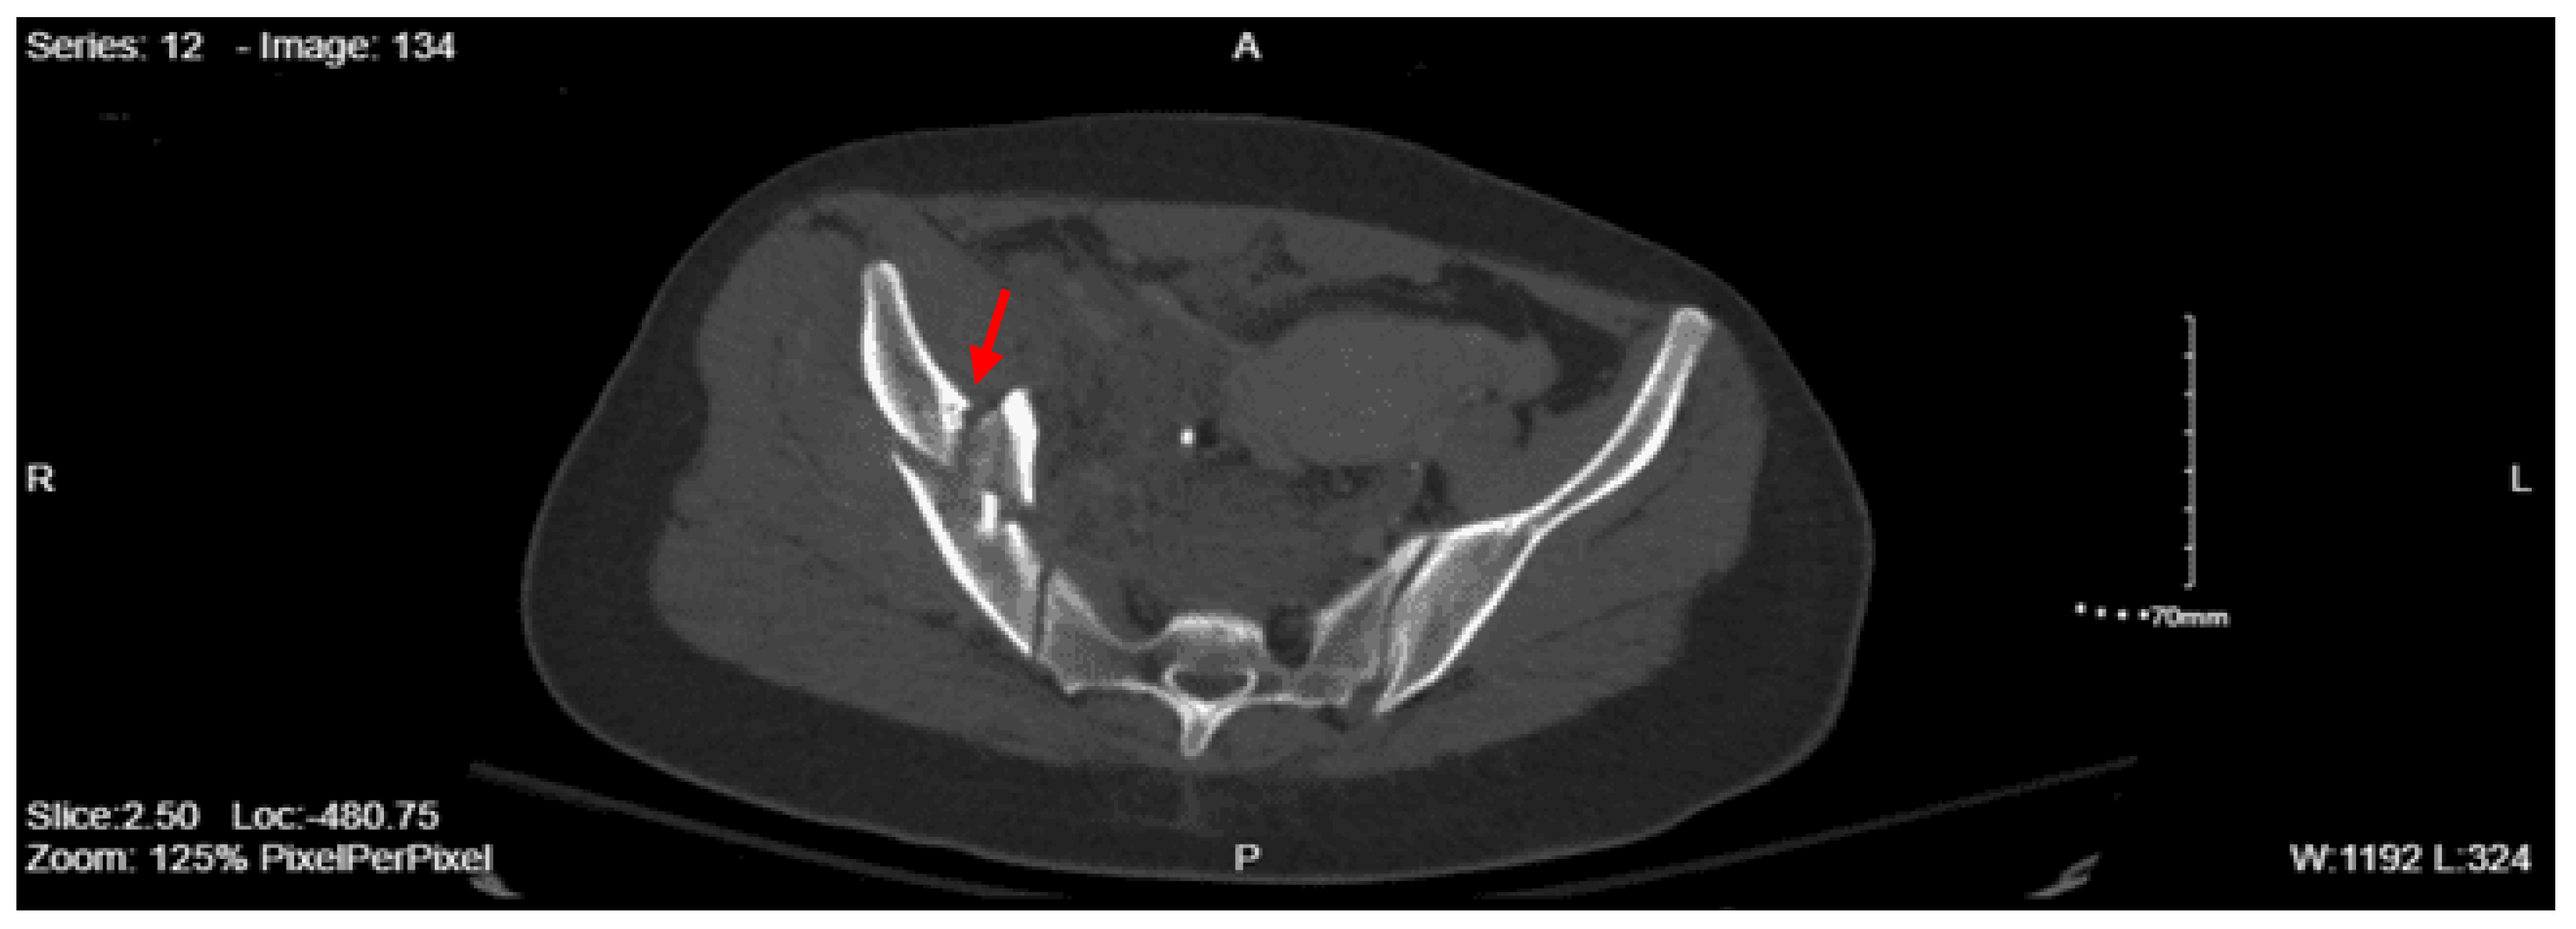

Imaging as shown in Figure 1, Figure 2 and Figure 3:

CT lumbar spine w/o contrast: An acute comminuted fracture is seen involving the superior portion of the left sacral wing. The SI joints are intact. Intact lumbar spine.

CT abdomen/pelvis with contrast: Acute fractures are seen involving the right superior pubic ramus and left inferior pubic ramus. An acute comminuted avulsed fracture of the left sacral wing in the superior and midportion is demonstrated. No definitive acute traumatic visceral abnormalities were found throughout the abdomen and pelvis.

XR pelvis: Nondisplaced superior ramus fractures. Nondisplaced left lateral sacral fracture.

DX: Denis zone II left sacral alar fx involving S1 foramina. AOSpine B3: NX, M3